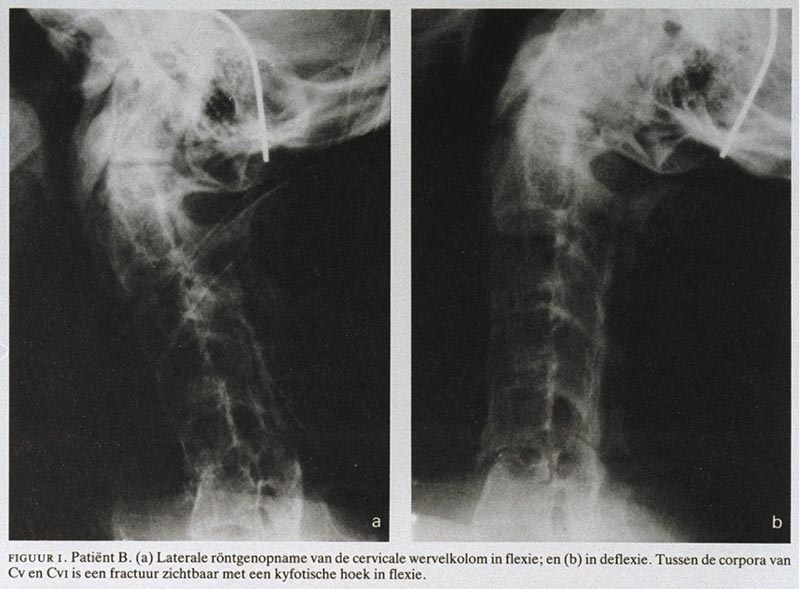

Een gevaarlijk stijve nek bij ziekte van Bechterew Nederlands Tijdschrift voor Geneeskunde